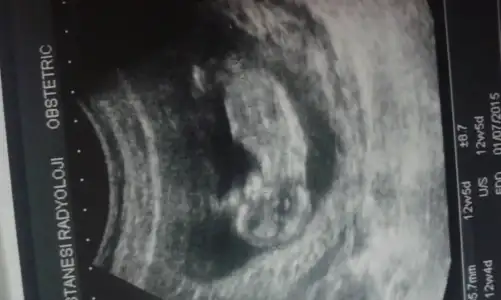

Kizlar merhaba daha oncede sordum ama kimse cevap vermedi benim bebegime de yorum yaparmisiniz

Senin görüntü de pek net değil ama erkek diyesim var

Resim kac haftalik canm kiz benc